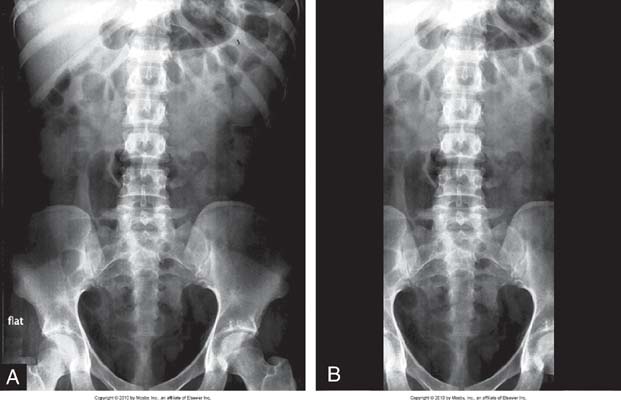

The terms beam restriction and collimation are used interchangeably; they refer to a decrease in the size of the projected radiation field. The term collimation is used more often than the term beam restriction because collimators are the most popular type of beam-restricting device. Increasing collimation means decreasing the field size, and decreasing collimation means increasing the field size (Fig. 7-2).

FIG. 7-2 A, Full view of the abdomen with decreased collimation when compared with B. B, Increased collimation of the abdominal region to image the lumbar spine. (From Bontrager K, Lapignano J: Textbook of Radiographic Positioning and Related Anatomy, ed 7, St. Louis, 2010, Elsevier.

In addition to decreasing the patient dose, beam-restricting devices reduce the amount of scatter radiation produced within the patient and reduce the amount of scatter to which the IR is exposed, thereby increasing radiographic contrast. The relationship between collimation (field size) and the quantity of scatter radiation is illustrated in Fig. 7-3. As previously stated, collimation means decreasing the size of the projected x-ray field; hence, increasing collimation means decreasing x-ray field size, and decreasing collimation means increasing x-ray field size.